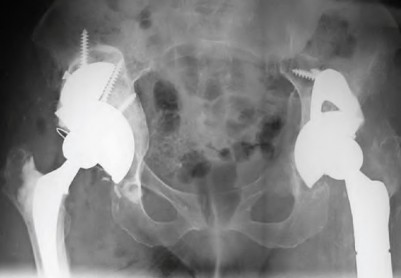

A 64-year-old woman with osteoarthritis underwent bilateral total knee replacement 3 years ago. Current radiographs are shown in Figure A. She reports a 3-month history of bilateral knee pain while at rest and increasing swelling in the knees. Her ESR and CRP are elevated and bilateral knee aspiration cultures reveal Staphylococcus aureus. What is the most likely outcome if the patient undergoes simultaneous, bilateral knee resection arthroplasty with cement spacer and a course of intravenous antibiotics?

This patient presents with bilateral total knee arthroplasty infection.

Wolff et al report Level 4 evidence of 18 patients followed an average of 5 years after bilateral TKA infection. Eleven patients were initially treated with attempts to salvage the original prosthesis (polyethylene l liner exchange, I&D, IV antibiotics and chronic oral suppressive antibiotics. With prosthesis retention, 9/11 (81%) developed recurrent infection at a mean of 15 months. The other 10 patients initially underwent resection arthroplasty with cement spacer and a course of IV antibiotics. Seven of the 10 (70%) underwent reimplantation at a mean of 3 months (6 weeks to 5 months) and none of the patients required revision at mean of two years follow up. Satisfaction rates were significantly higher among this group of patients. The authors advocate the protocol of bilateral TKA resection arthroplasty with cement antibiotic spacer and course of IV antibiotics followed by prosthesis reimplantation.